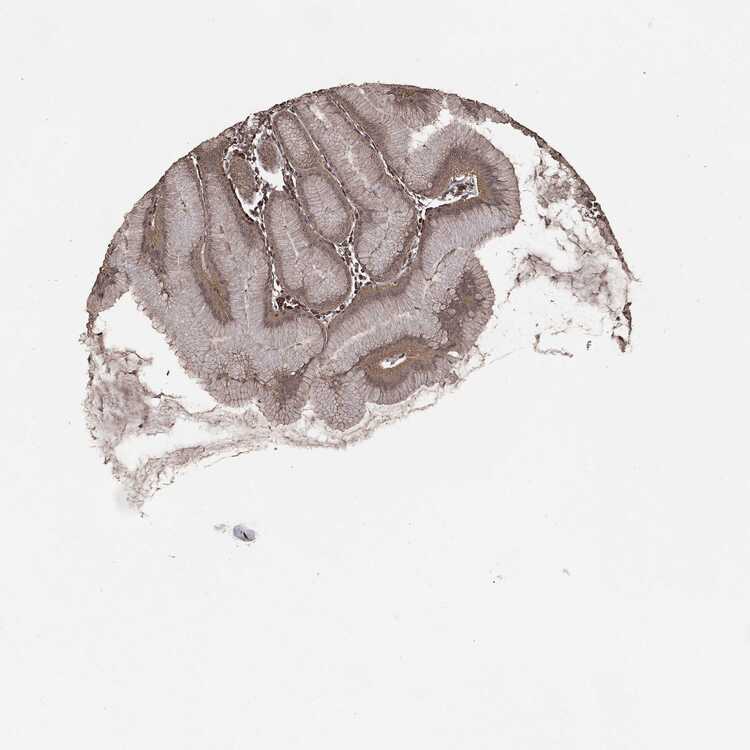

STOMACH 2 - Antibody stainingi

Antibody staining in the annotated cell types in the current human tissue is reported as not detected, low, medium, or high, based on conventional immunohistochemistry profiling in selected tissues. This score is based on the combination of the staining intensity and fraction of stained cells.

Each image is clickable and will lead to virtual microscopy that enables deeper exploration of all samples and also displays staining intensity scores, fraction scores and subcellular localization as well as patient and tissue information for each sample.

Antibody CAB069425Antibody CAB080053Antibody CAB080065Antibody CAB080070Antibody CAB080081Antibody CAB080095Antibody CAB080097

Glandular cells HighMediumMediumMediumLowMediumHigh